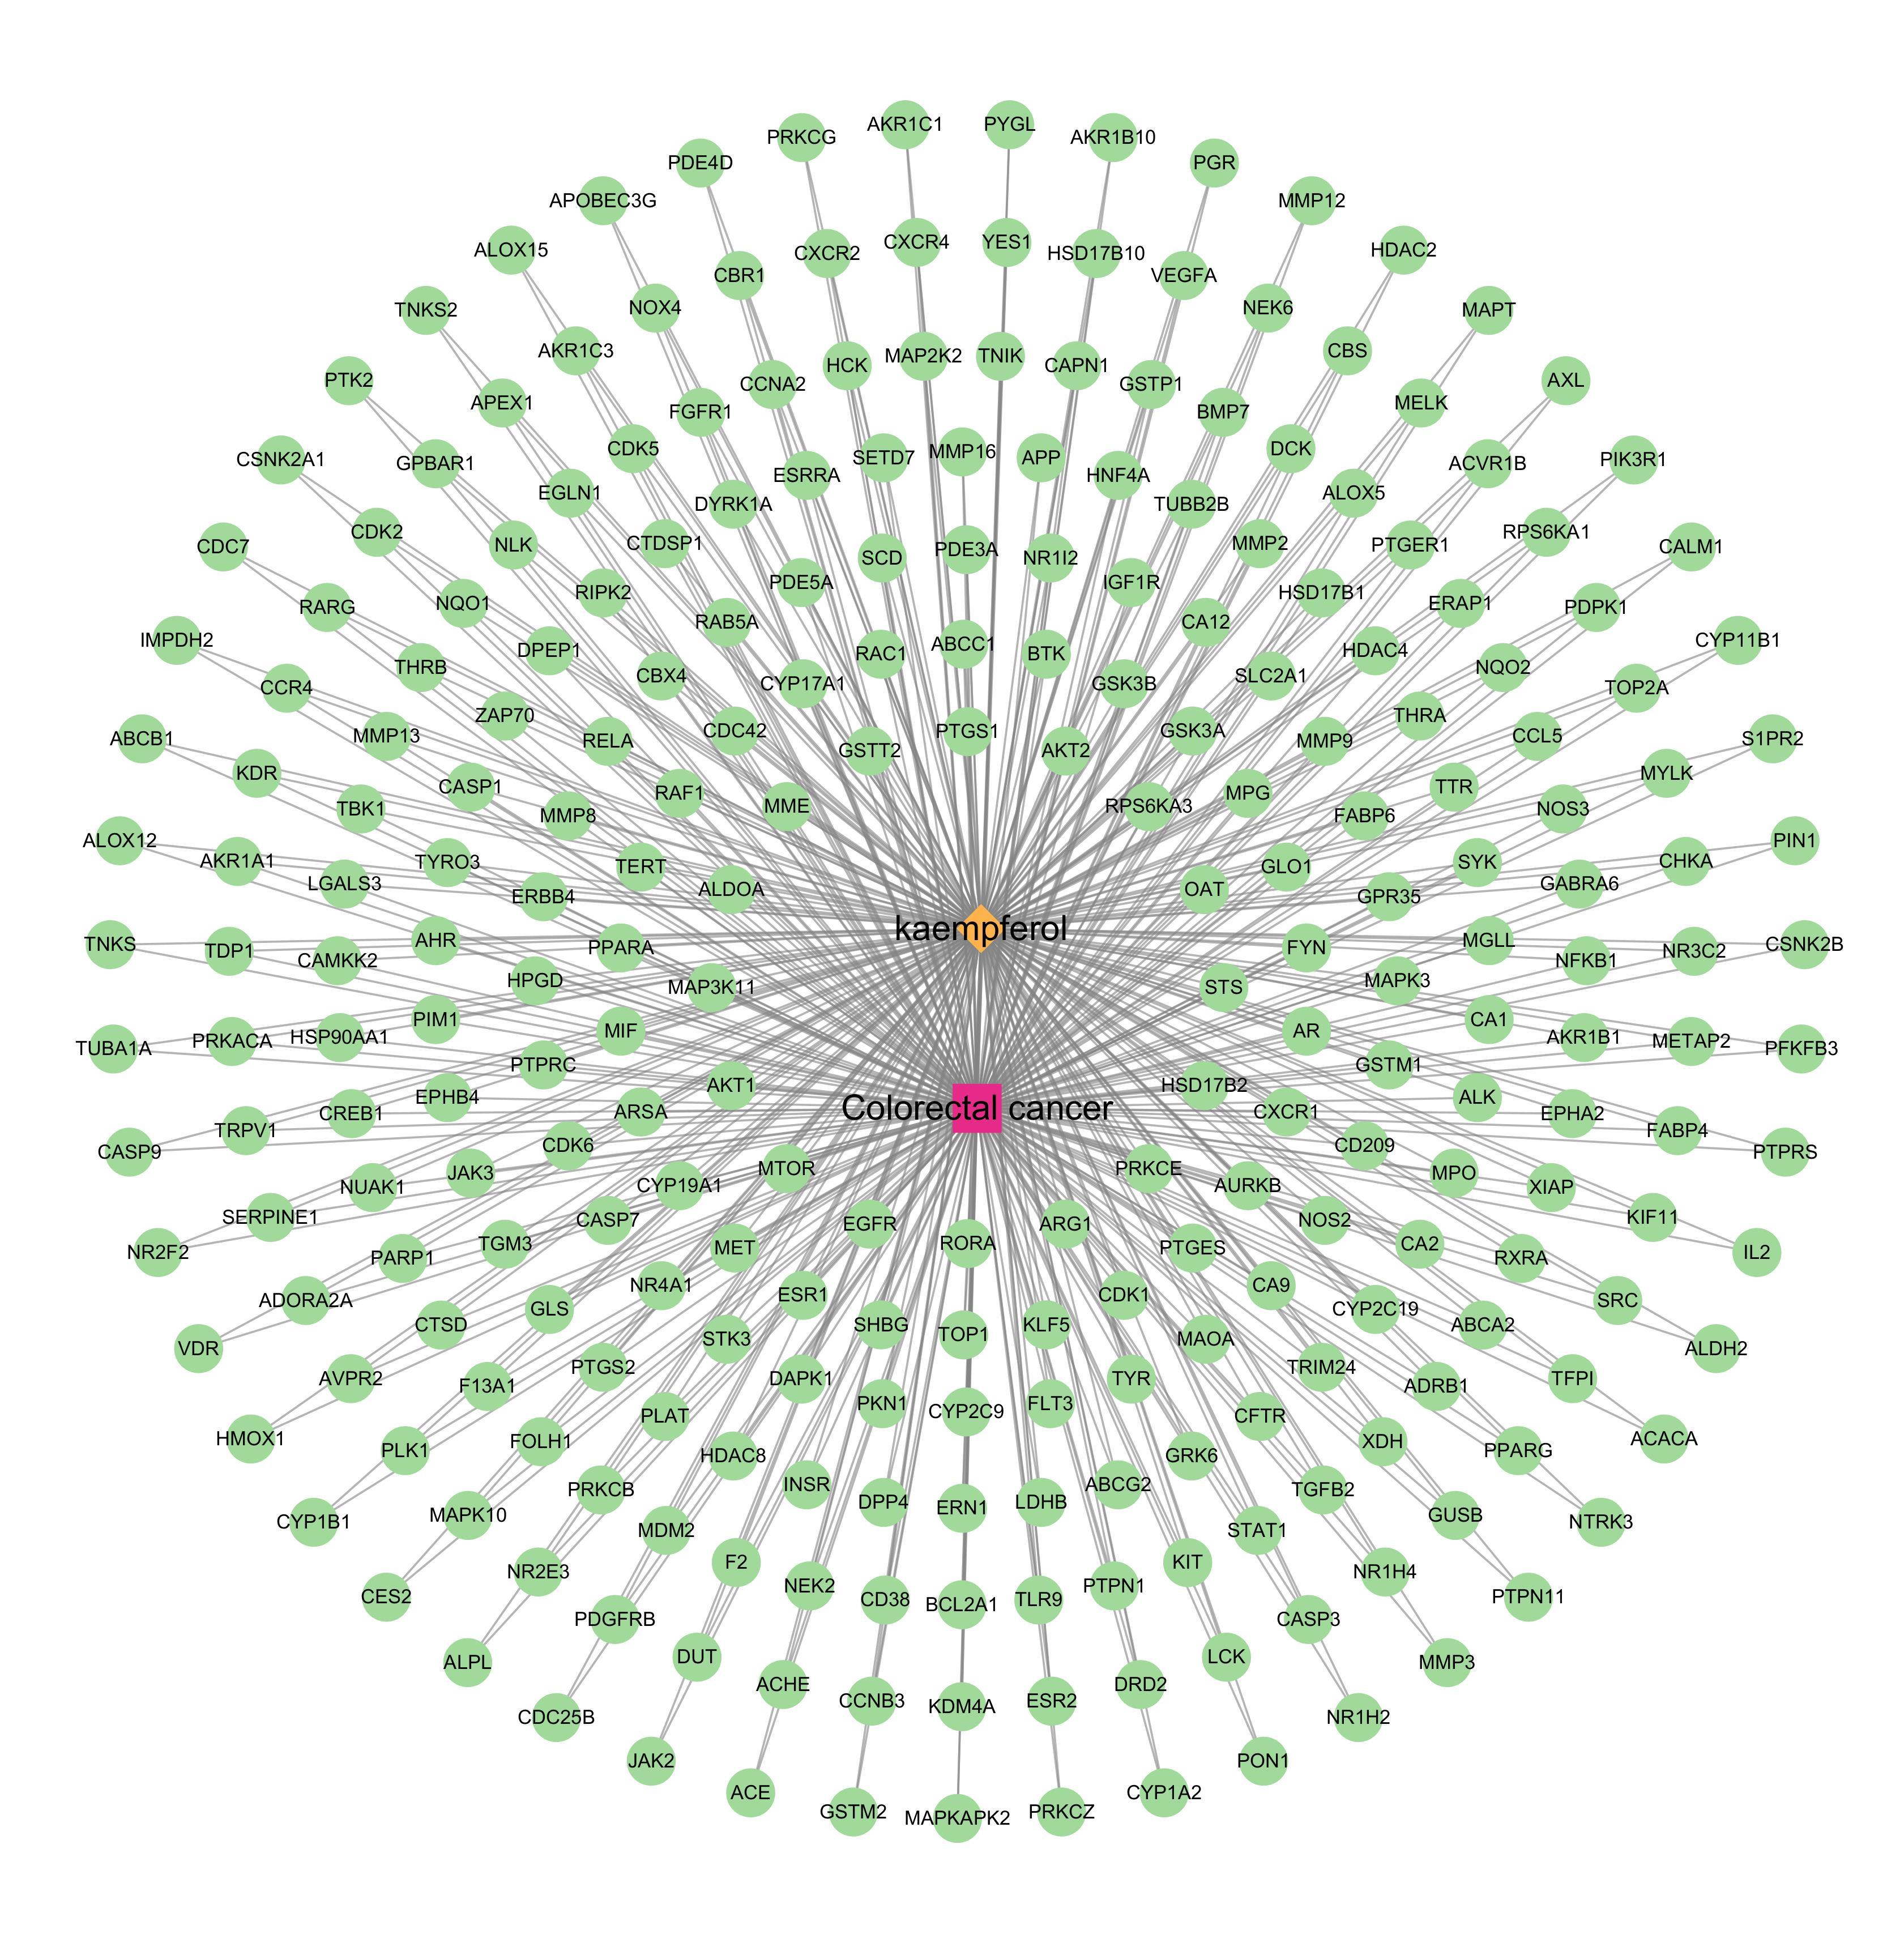

摘要:背景与目的 结直肠癌(CRC)发病率持续上升,晚期患者疗效有限,迫切需要开发新的抗肿瘤药物。山柰酚是一种天然黄酮类化合物,具有抗氧化、抗炎及抗癌活性。本研究结合网络药理学与实验验证,系统探讨山柰酚抗CRC的关键靶点及潜在机制。方法 通过SwissTargetPrediction、SEA、PharmMapper、TargetNet等数据库筛选山柰酚潜在靶点,从GeneCards、OMIM、CTD、DrugBank数据库获取CRC相关靶点,取交集构建“化合物-靶点-疾病”网络。利用STRING数据库和Cytoscape软件分析蛋白质-蛋白质相互作用(PPI)并筛选核心靶点,进一步进行GO与KEGG富集分析。采用人CRC HCT-116细胞进行CCK-8、克隆形成、划痕、Transwell实验及Western blot检测,验证山柰酚对细胞增殖、迁移、侵袭及凋亡相关蛋白表达的影响。结果 共筛得山柰酚作用靶点492个、CRC相关靶点5 078个,交集269个。PPI分析鉴定出Akt1、HSP90AA1、ESR1、SRC、CASP3、NFKB1等53个核心靶点。GO分析提示这些靶点主要参与细胞应激反应、凋亡与氧化应激调控;KEGG分析显示主要涉及化学致癌-受体活化、催乳素、雌激素及PI3K/Akt信号通路。细胞实验证实山柰酚能明显抑制HCT-116细胞的增殖、克隆形成、迁移与侵袭能力(均P<0.05),呈浓度依赖关系,并下调Bcl-2和cyclin D1、上调Bax的表达(均P<0.05)。结论 山柰酚可通过多靶点、多通路协同作用抑制CRC细胞的增殖、迁移与侵袭,并诱导凋亡,其机制可能与调控PI3K/Akt及雌激素信号通路等密切相关。本研究为山柰酚作为CRC潜在治疗药物提供了理论依据与实验支持。